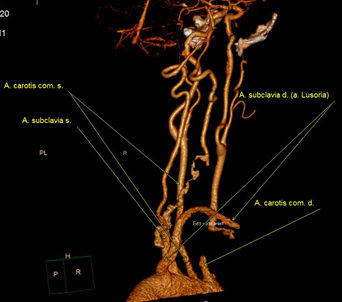

В послеоперационном периоде больная была дополнительно обследована: выполнена компьютерная томография шеи и органов грудной клетки с ангиографией (рис. 3 а, б) и прямая ангиография (рис. 4), по данным которых подтверждено наличие у пациентки аномалии развития ветвей аорты. Правая подключичная артерия отходит от уровня перешейка аорты по ее задней поверхности самостоятельным стволом, проходя между аортой и позвоночным столбом на уровне третьего позвонка, – a. lusoria. От правой подключичной артерии отходит правая позвоночная артерия. Правая общая сонная артерия отходила от аорты одним устьем вместе с левой общей сонной артерией, что наглядно демонстрируется на ангиограммах в виде симптома “бычьих рогов”. Послеоперационный период у больной протекал гладко, без осложнений. Фонация голосовых связок не была изменена.

Рис. 3. Результаты компьютерной томографии шеи и органов грудной клетки с ангиографией: а – аорта (вид сзади); б – предпозвоночное расположение правой подключичной артерии.